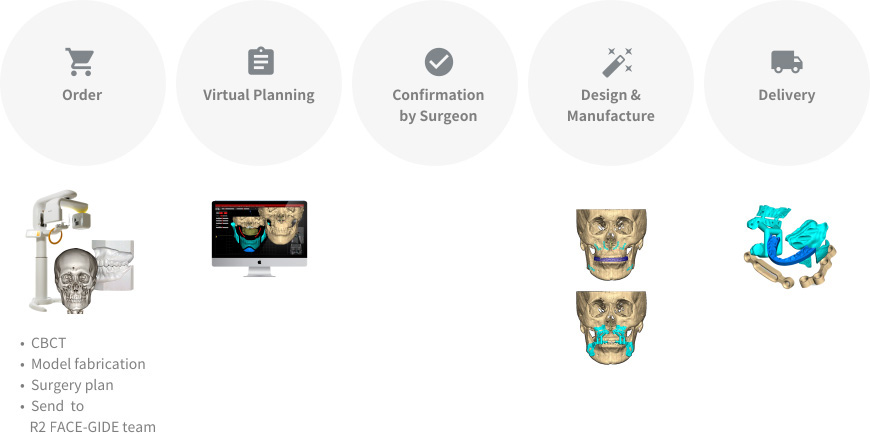

R2STUDIO digital work flow

Step01

Data Collection

- CBCT

- Face scan

- Impression scan

Step02

Starting Point

- CBCT reorientation

- Natural head position

- 3D facial matching

Step03

Facial Analysis

- Facial pattern analysis

- Treatment planning

Step04

Jaw Setup

- Jaw segmentation

- Jaw setup

Step05

User Confirmation

- User confirmation via FACEGIDE viewer

Step06

FACEGIDE Services

- Design-customized saw guides & plates

- Manufacturing (3D printing or milling) of saw guides & plates

3D Jaw Setup & Review

- Send R2 STUDIO data & simple surgery plan to R2 Center & receive 3D jaw setup file within 24 hours

- Use FACEGIDE review program to confirm 3D jaw setup file